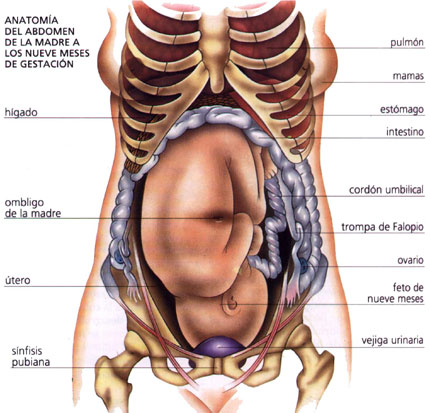

Физиология беременности: строение органов